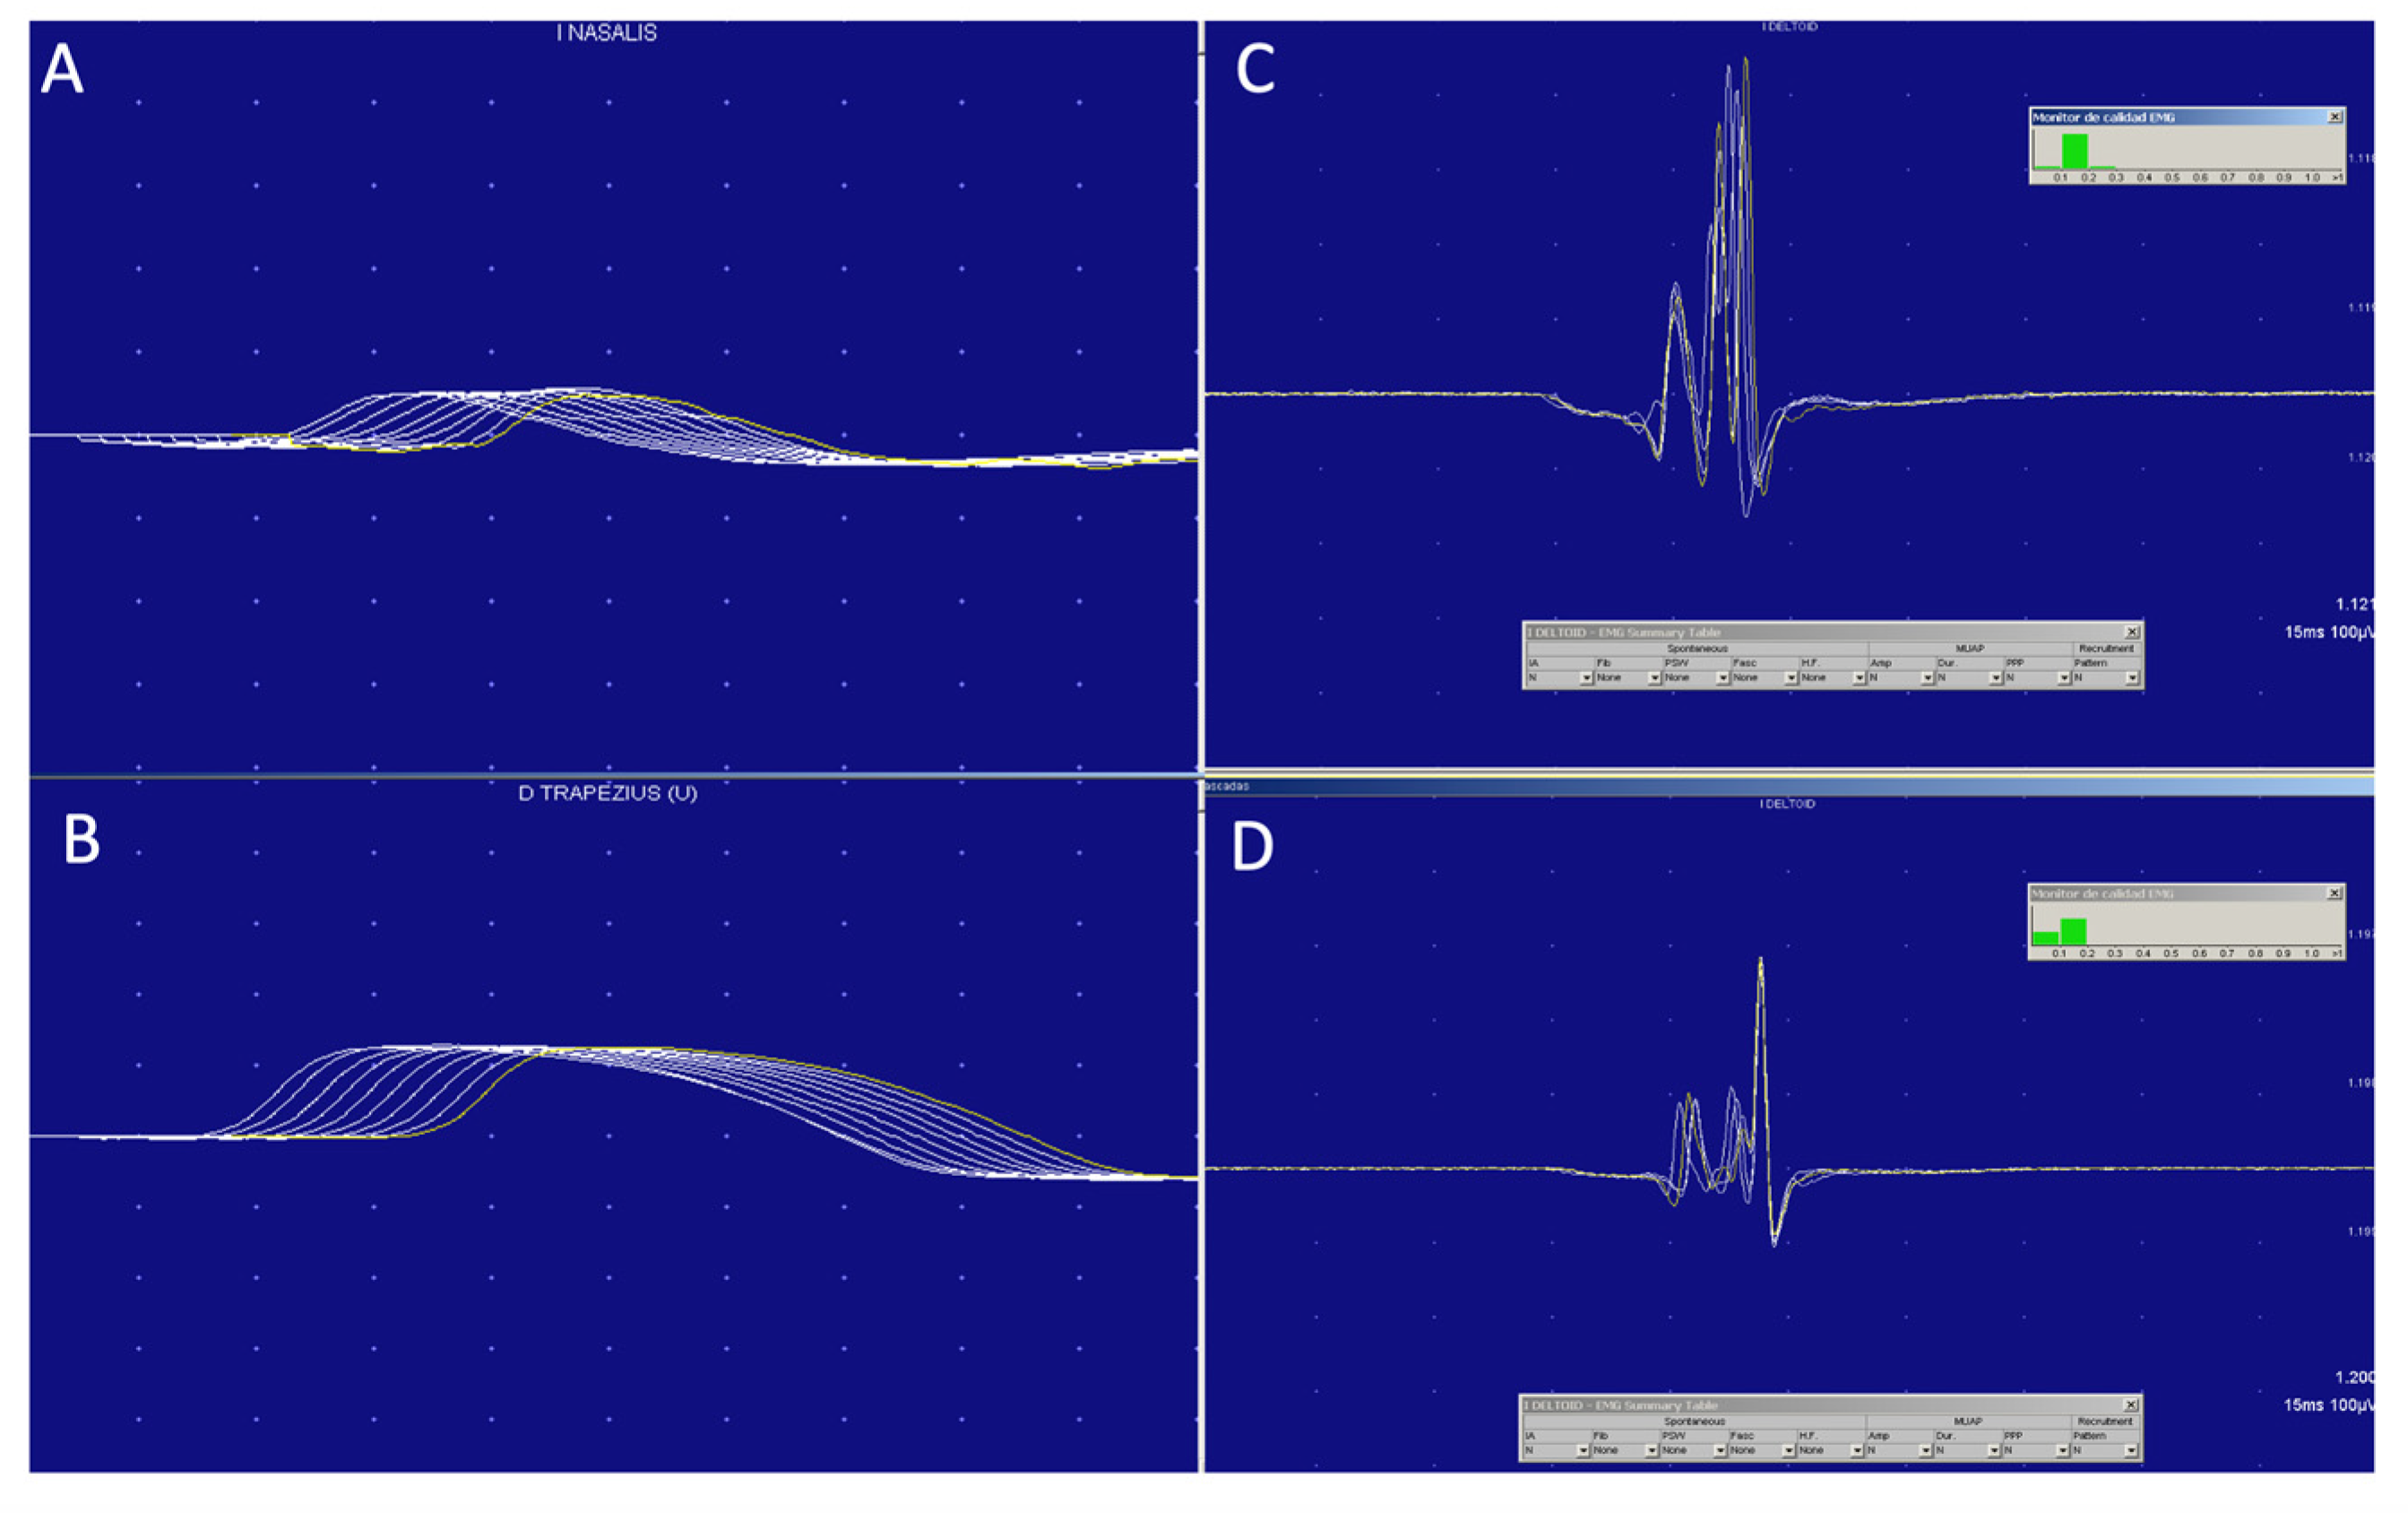

3.3. Electrophysiological Tests

| EMG | Myopathic | Myopathic | Myopathic | Normal | Myopathic | Myopathic |

| RNS 3 Hz/Jitter | N/NA | N/NA | N/Jiggle | N/NA | N/Pathological | N/Pathological |